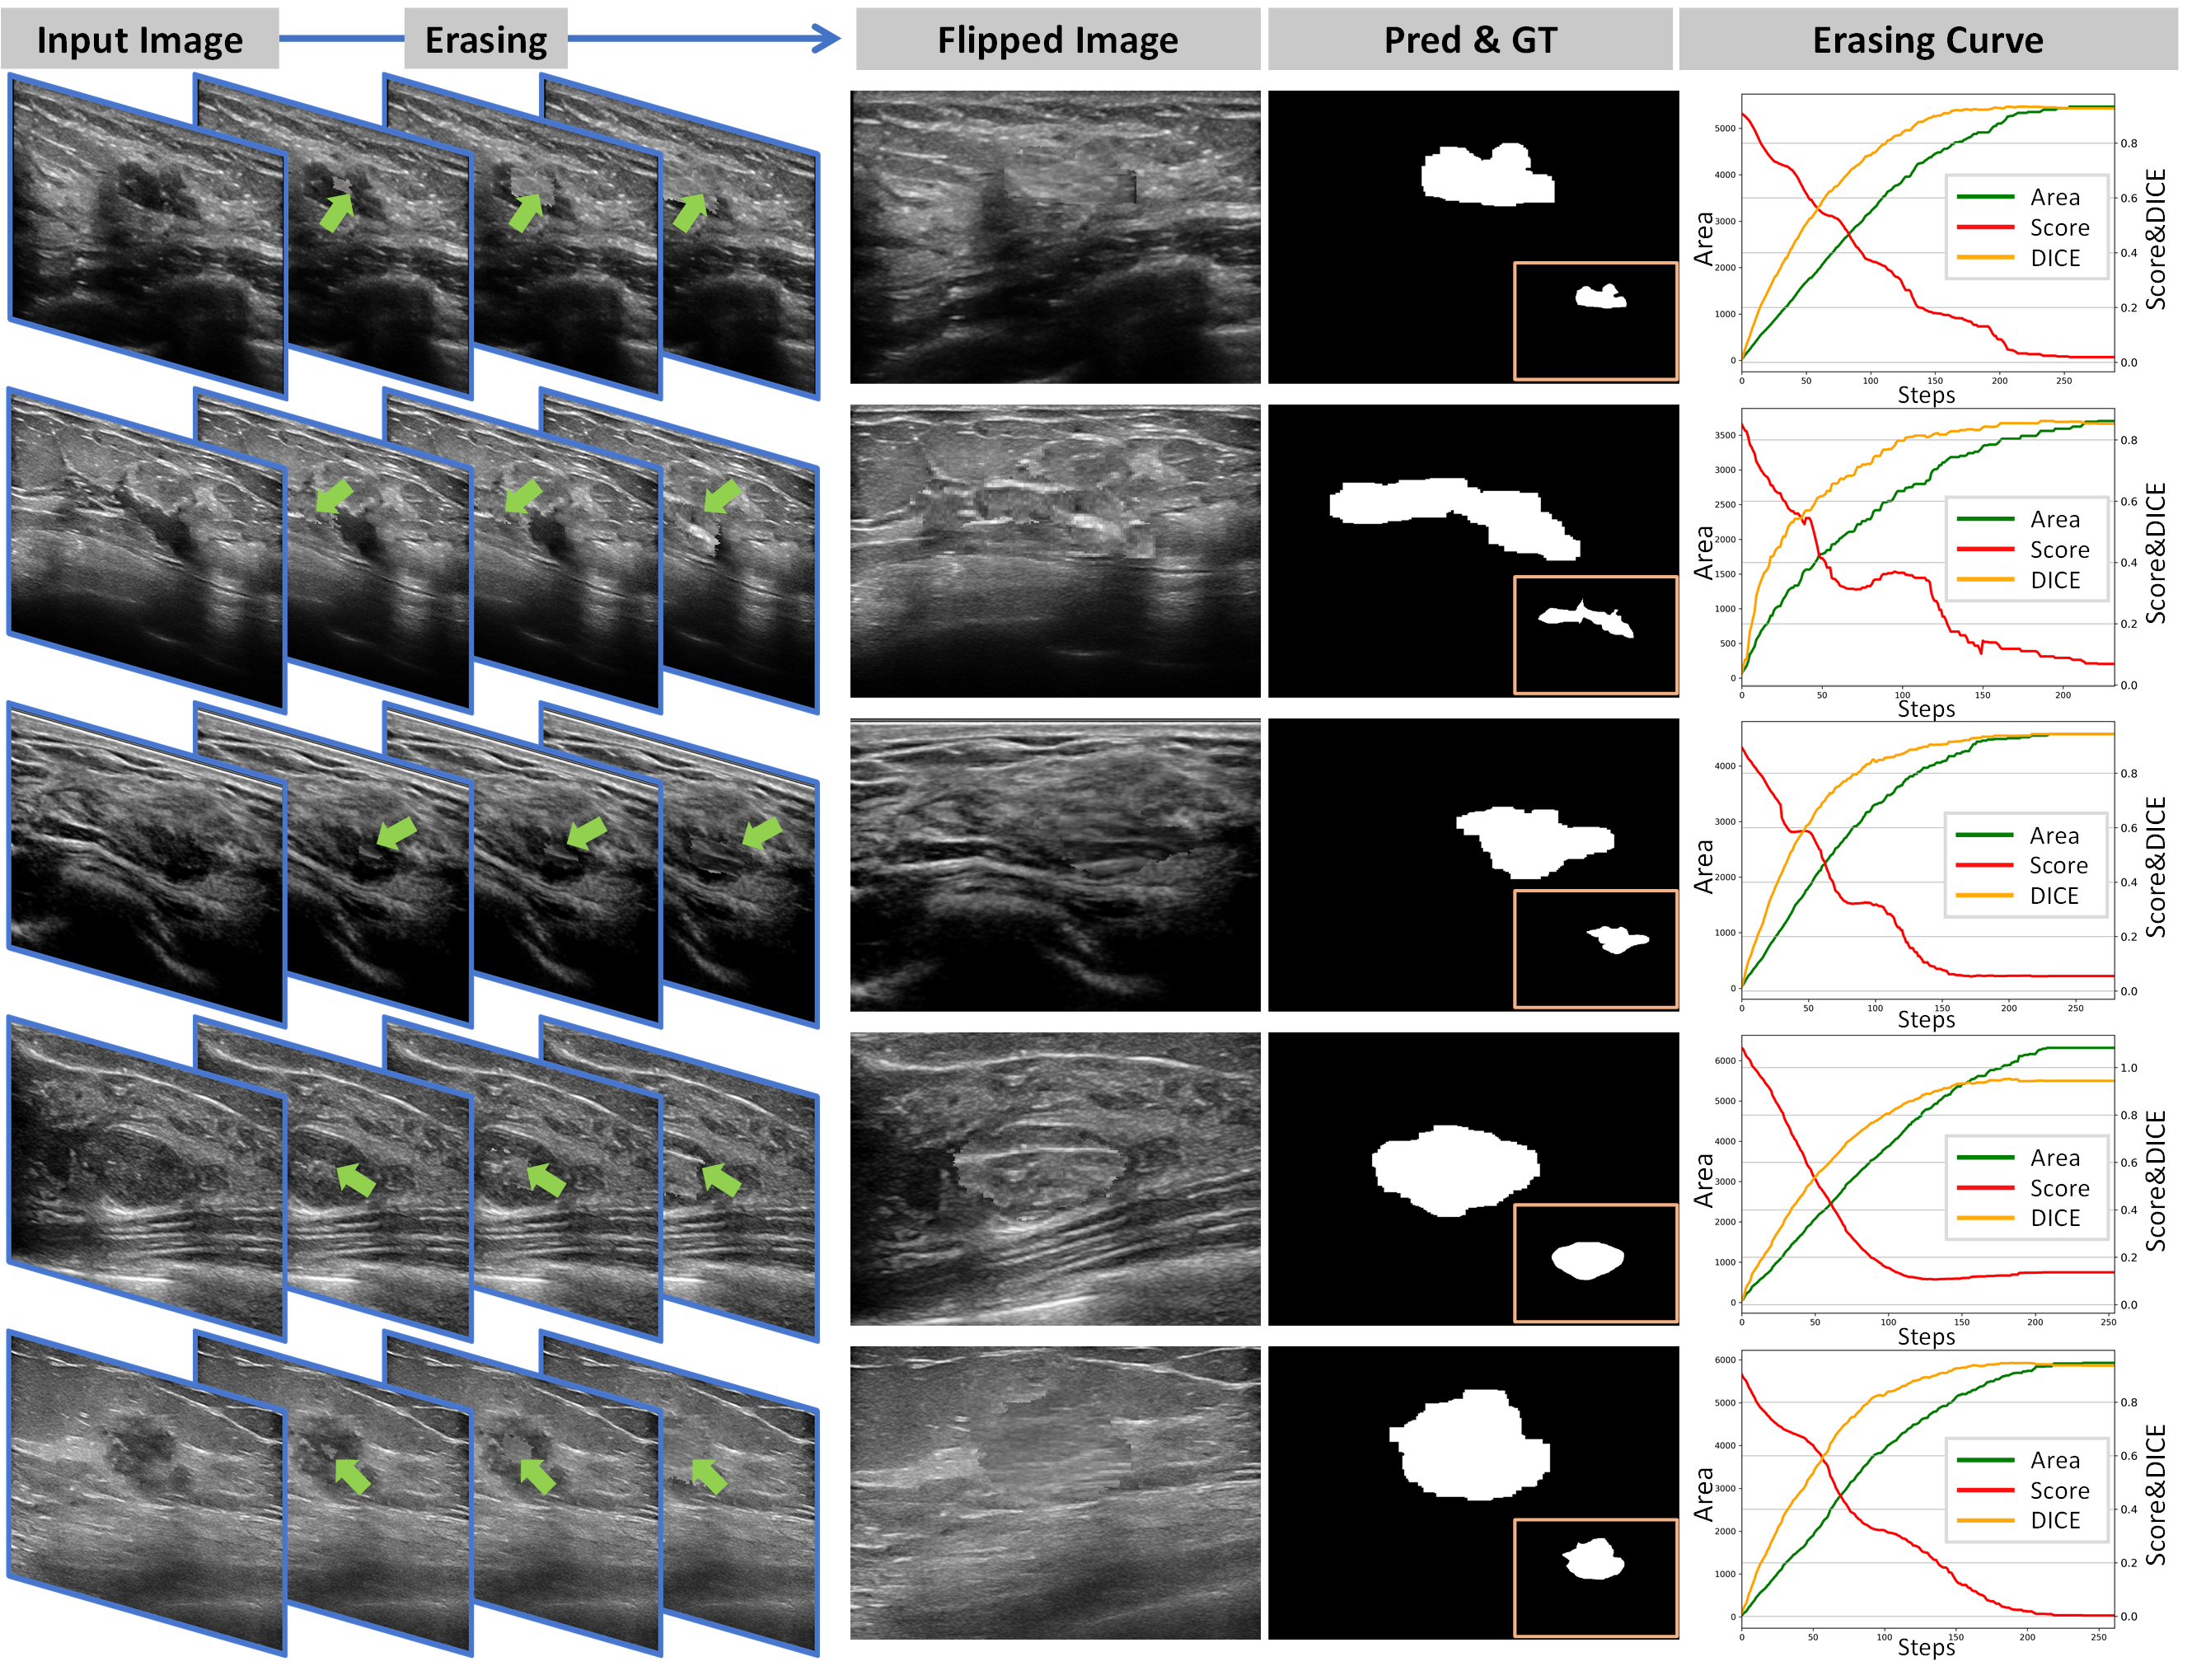

Fig. 9: Five typical cases with good BUS nodule segmentation results. For each case (row), columns 1-4 visualize the erasing process in different steps. Columns 5 and 6 show the final predicted masks and GTs. The last column visualizes the erasing curves.

The visualization results are depicted in Figure 8. The results indicate that Ours outperforms the strong competitors, including traditional methods, CAM- and box-based WSS approaches, and the SAM-based foundation model. Besides, Ours can achieve comparable performance with the fully-supervised method (Unet) and even excels in certain instances (e.g., row 1 in Figure 8). Furthermore, we present the input images, erasing process, flipped images, predictions & GTs, and erasing curves for five typical cases in Figure 9. The green arrows in the erasing process highlight the region erased by the agents at different steps. Nodules in the input images (column 1) are erased, resulting in obtaining the flipped images (normal-like). Subsequently, the final erased region is extracted as the prediction, which closely resembles the GT (see column 6). The curves depicted in the last part illustrate the relationship between the size of the erased area (green), the DICE metric (yellow), and the nodule classification score (red). It is evident that as the erasing progresses, both the DICE and the erased area show a simultaneous increase, indicating a synchronous variation. Moreover, the classification score exhibits a continuous decline, with the classification tag transitioning from “nodule” to “normal tissue”. This observation validates the effectiveness of our proposed Flip Learning approach.